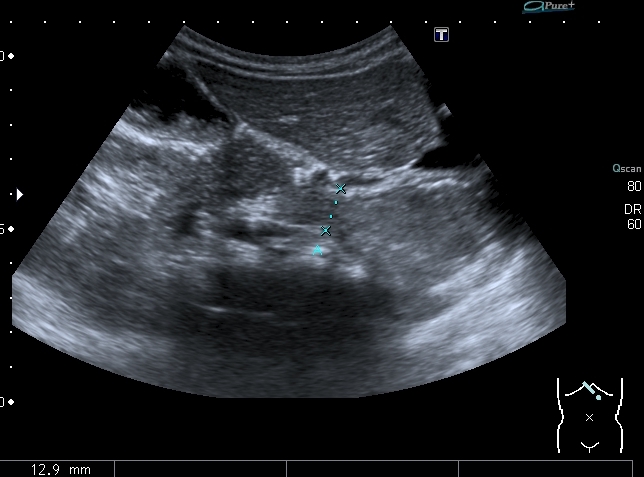

Сканы через пищеводное отверстие диафрагмы